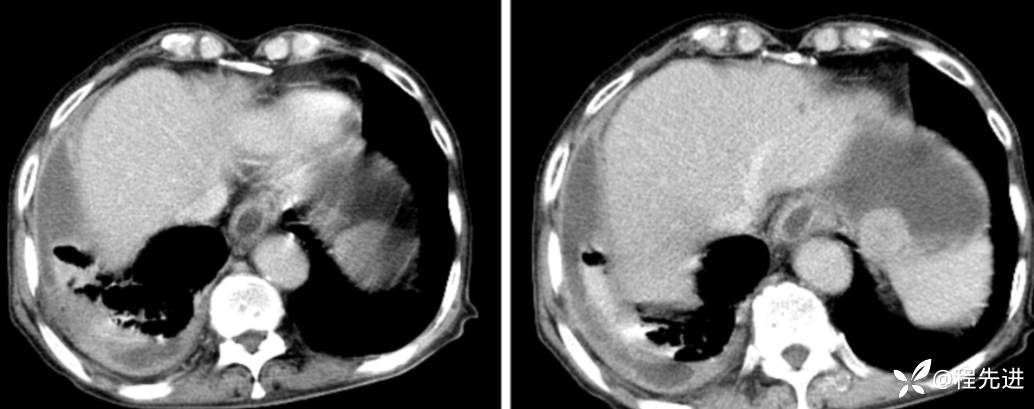

延迟期

局部放大